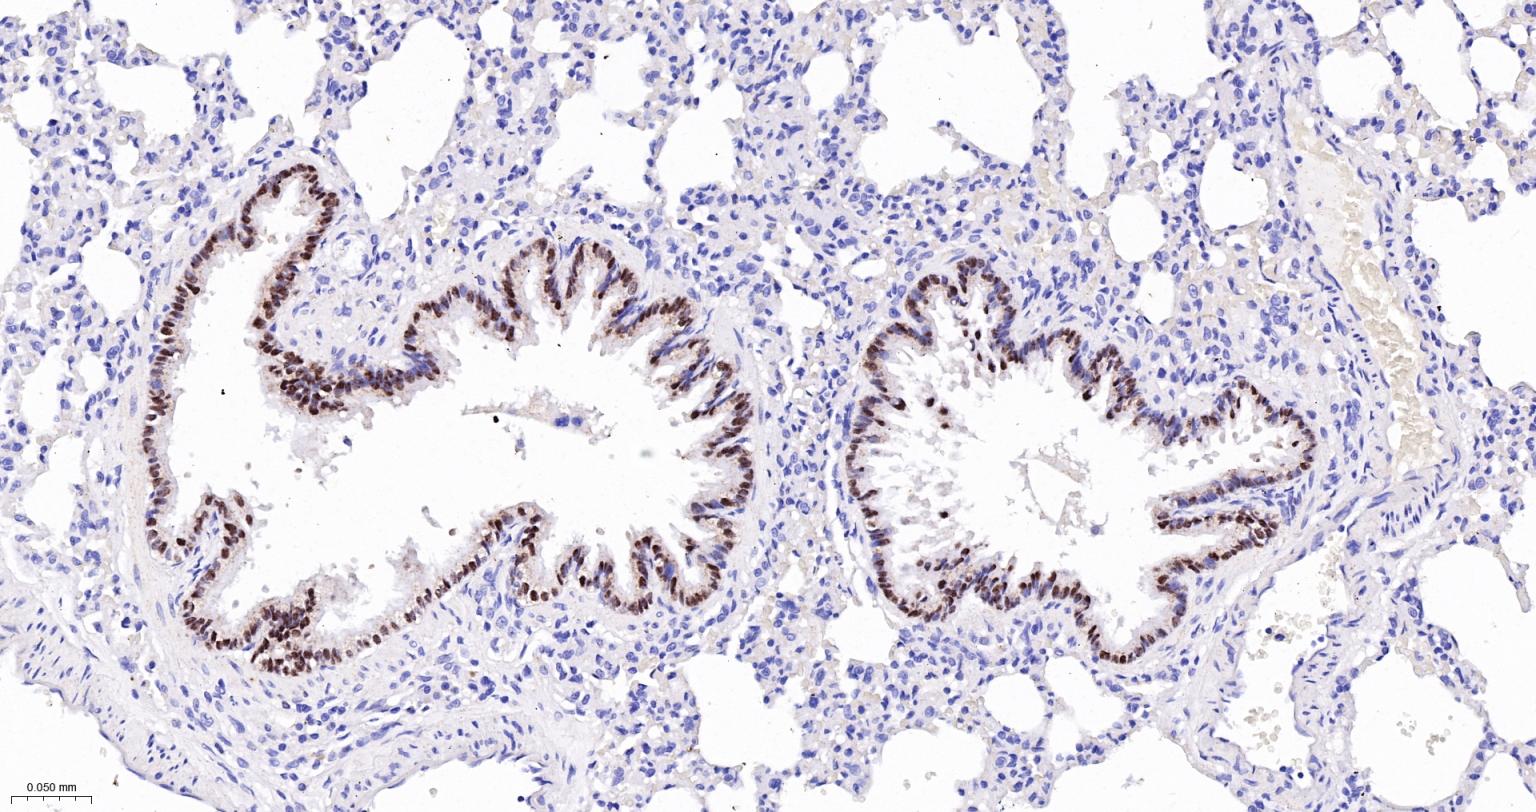

| IHC-P | Human, Mouse, Rat | 1:200-800 | |

| IHC-F | Human, Mouse, Rat | 1:200-800 | |